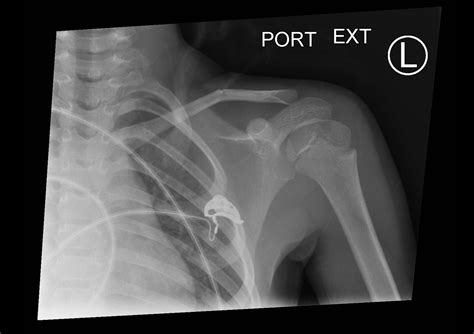

Diagnosing a broken collarbone in a newborn involves a physical examination and imaging tests. The healthcare provider will:

• Examine the baby's collarbone area for swelling, tenderness, and deformity

• Order an X-ray to confirm the fracture and assess its severity

In some cases, additional imaging tests such as an ultrasound or CT scan may be recommended to get a more detailed view of the injury.